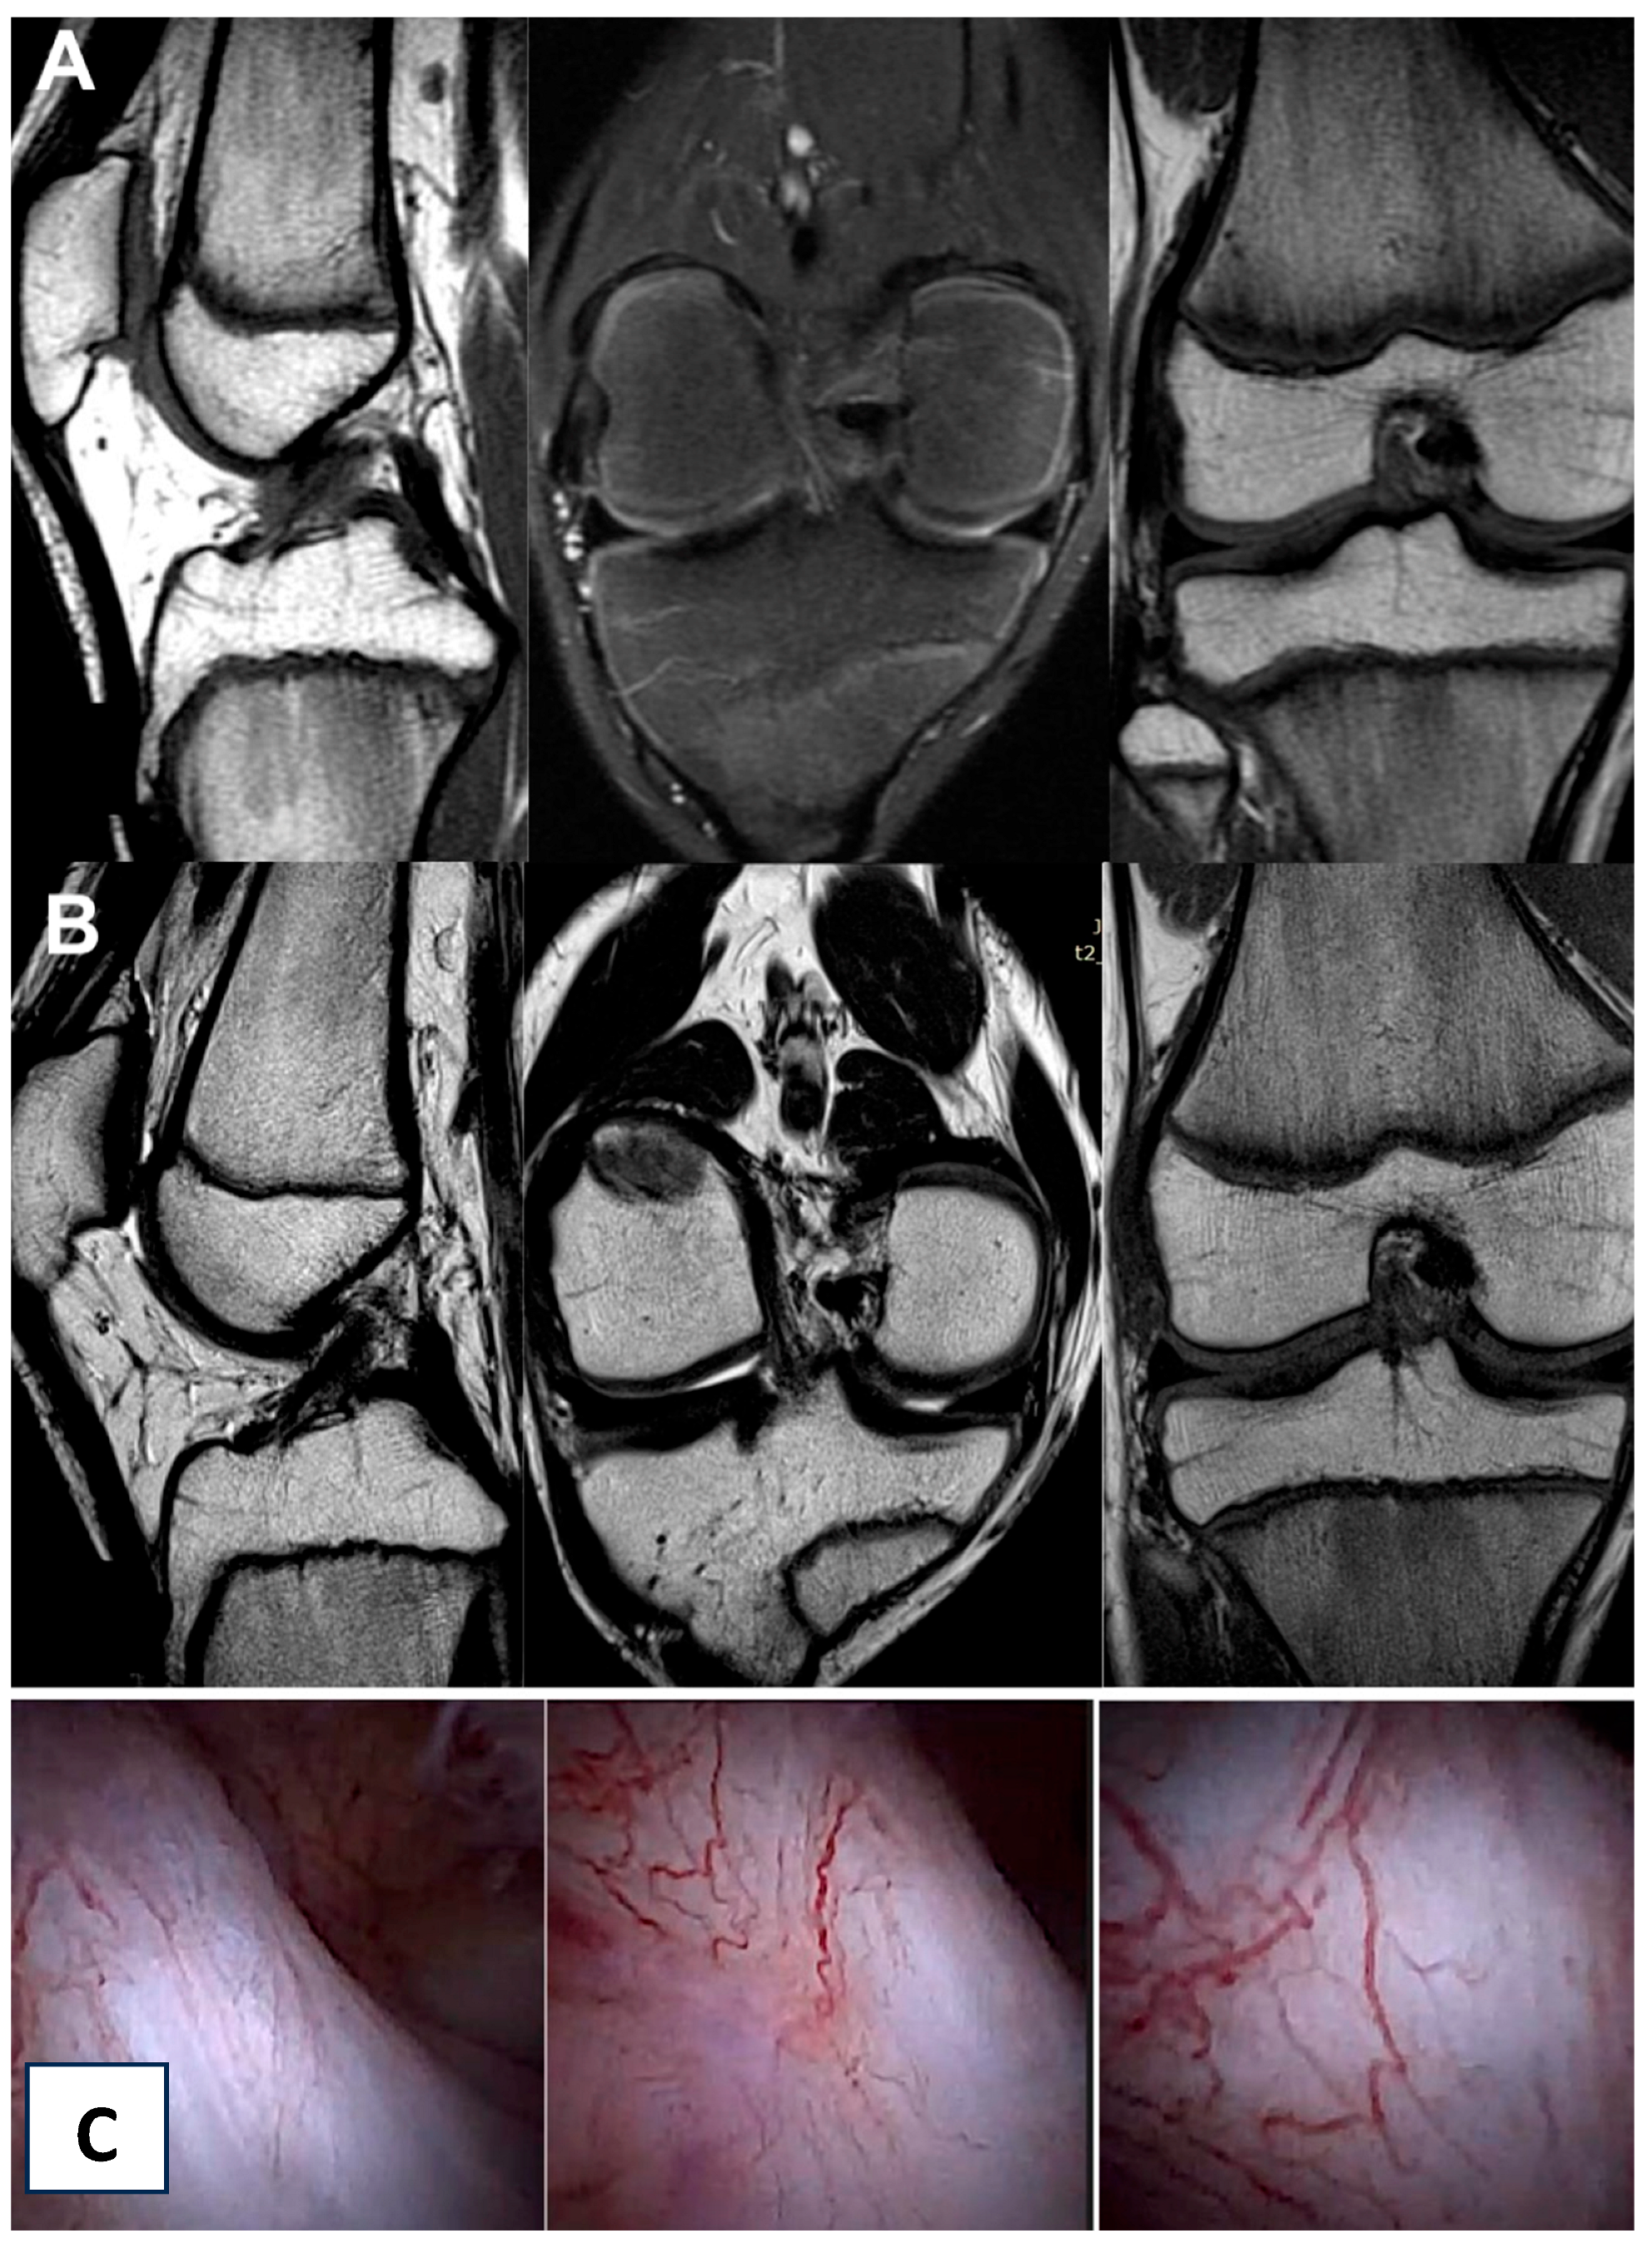

Figure 3.

The same knee MRI scans of a patient with an anterior cruciate ligament tear before treatment (A) and corresponding MRI scans after nanosurgery treatment with an RP-hCM injection (B). A nanoscopic view of the normal, healed ACL (C).